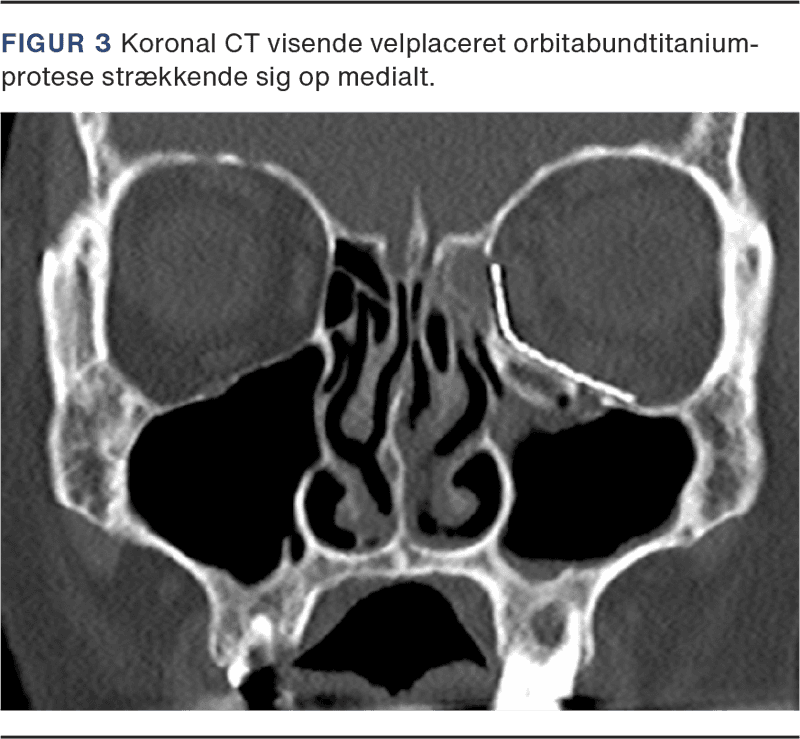

Mange BOF behandles konservativt, idet symptomerne kan være yderst begrænsede. Kirurgisk behandling sker oftest med konjunktival adgang posteriort for tarsalpladen og med indlæggelse af en præformet titaniumorbitabundprotese, som fikseres til nedre orbitakant med skruer. Indgrebet udføres, når frakturen er større end ca. 1 cm2 samt ved udtalt dobbeltsyn. Ved truet syn opereres akut og ved trap-door foretages indgrebet subakut for at begrænse muskelskade [9]. Postoperativ CT viser protesens beliggenhed, og efter ca. 14 dage udføres kontrol for dobbeltsyn ved øjenlæge (Figur 3).